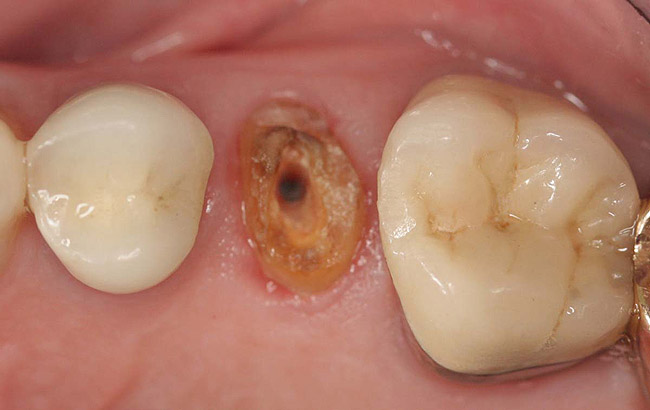

Case 1

A Class IN maxillary bicuspid was previously restored with a fiber post and an all-porcelain crown (Figure 1). The forces of the oral environment resulted in fracture of the fiber post and crown failure. The remaining fiber post in the root was removed, and anti-rotational areas were prepared for a cast post (Figure 2). A gold cast post was constructed at a dental laboratory, using an indirect technique (Figure 3). A porcelain-fused-to-metal (PFM) crown was constructed with a bevel finish to provide a ferrule and reduce forces on the post (Figure 4 and Figure 5).

Figure 2  Same second bicuspid as Figure 1 after removal of the fractured fiber post.

Figure 2